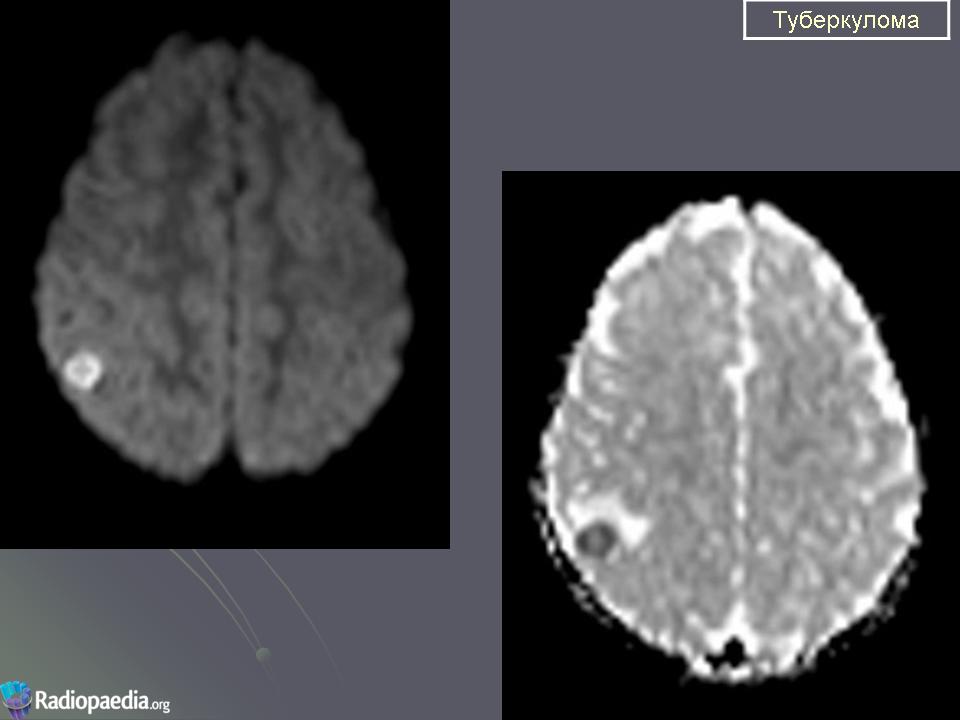

Туберкулёз ЦНС